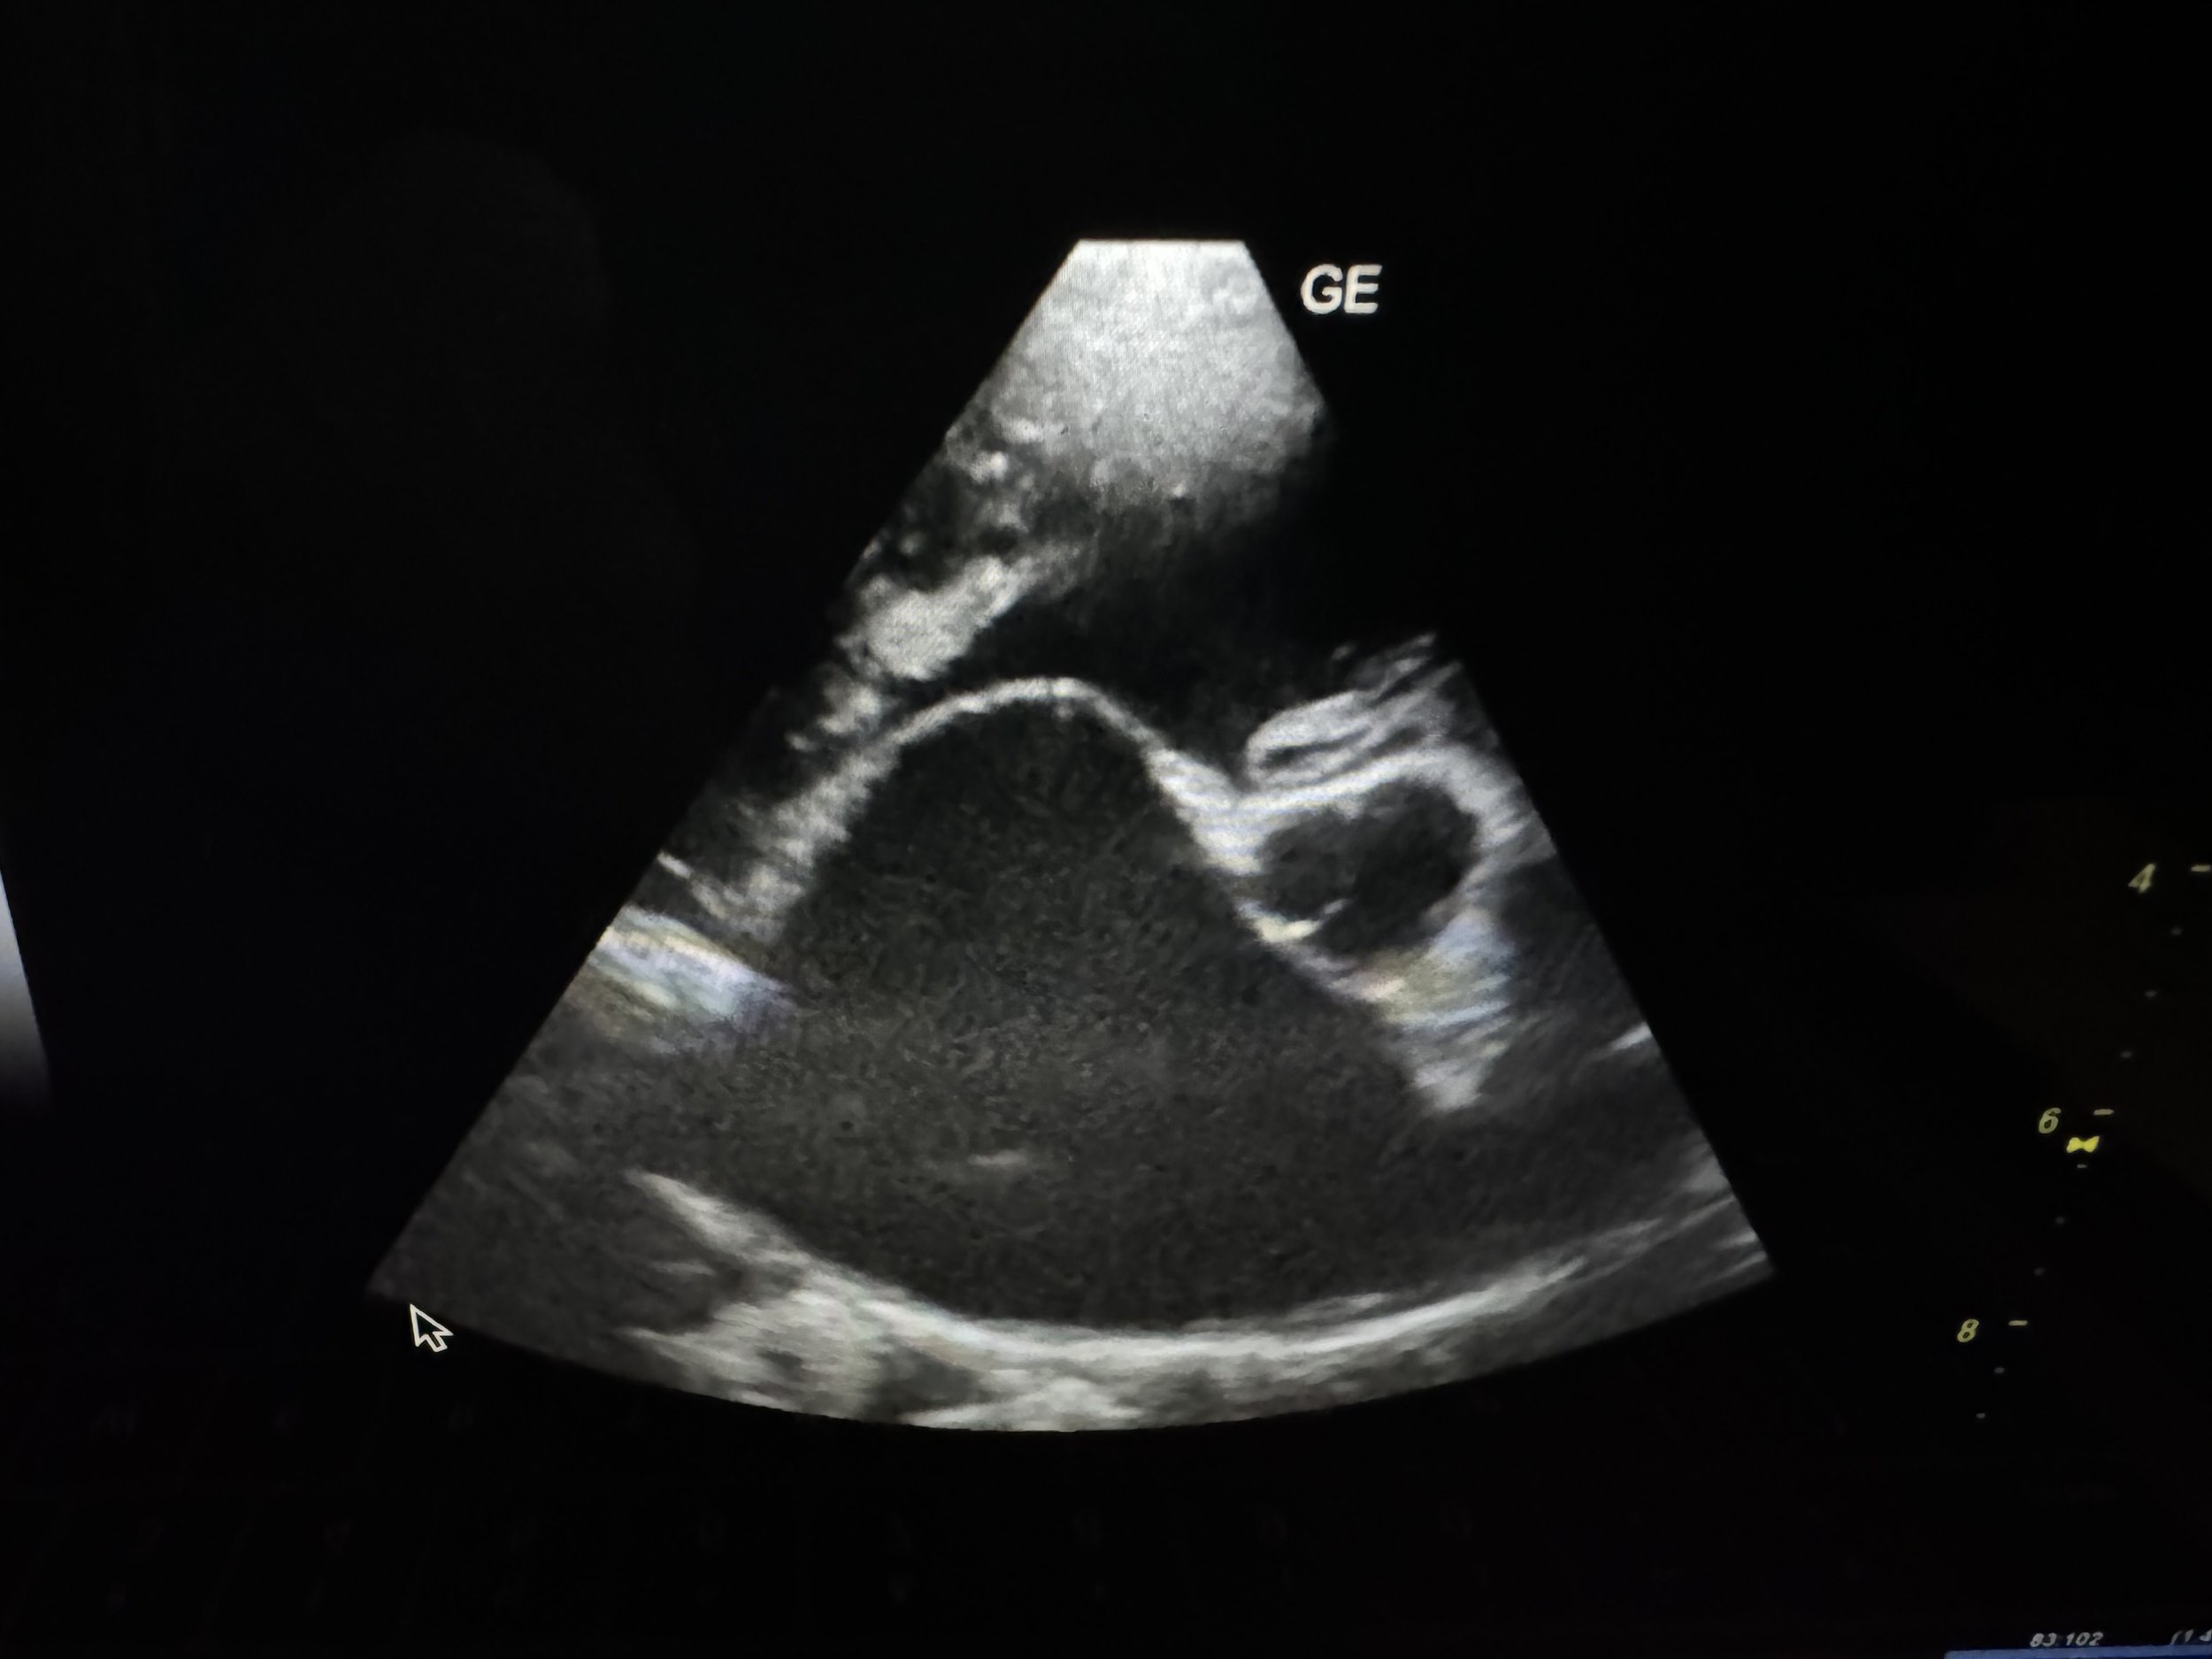

Ultrasound image of a fetus inside the womb.

• Imaging: POCUS, radiographs